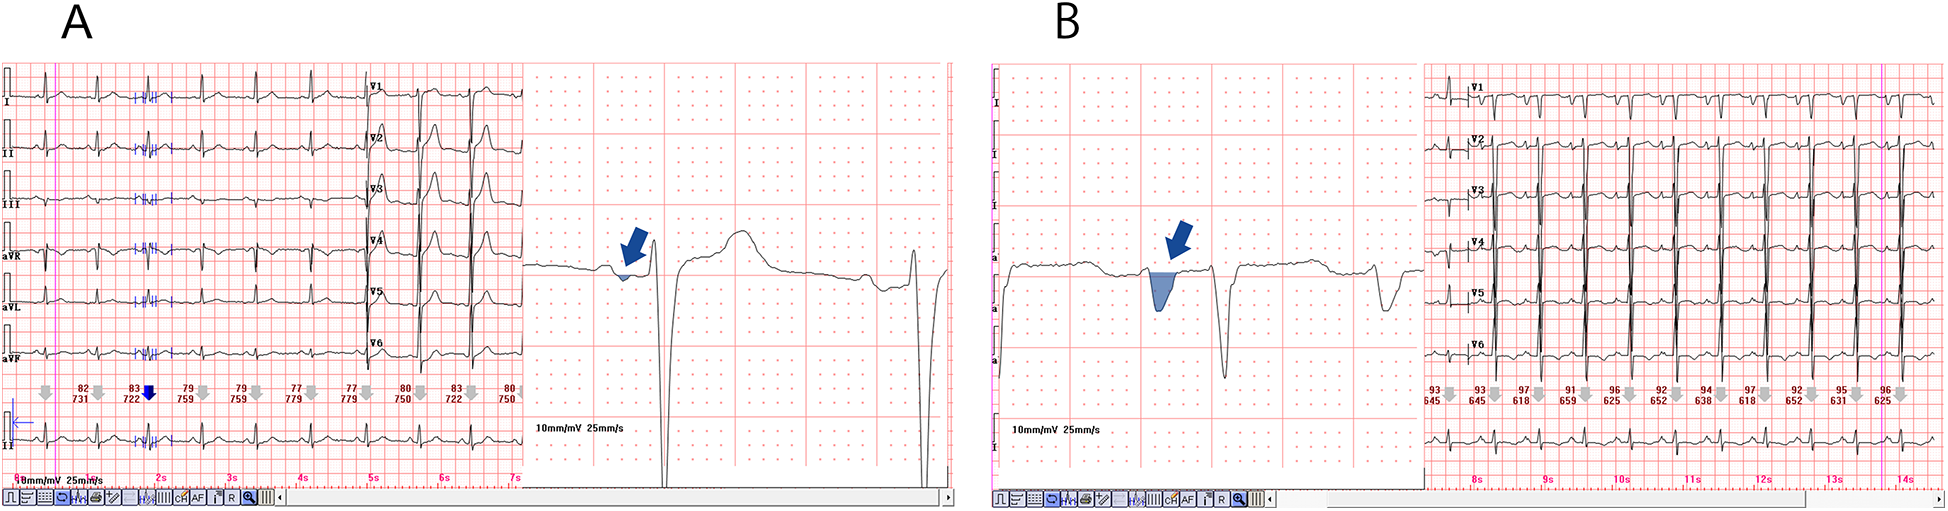

PWD serves as a direct and reliable measure of atrial conduction time, with numerous studies demonstrating a positive correlation between both the presence and severity of OSAHS and P-wave prolongation observed on a 12-lead ECG. This prolongation, coupled with uneven sinus node excitation, may predispose patients to atrial arrhythmias (29). Apneic episodes impose increased mechanical and pressure load on the left atrium, leading to structural remodeling and prolonged PWD, and have been identified as independent predictors of atrial scar formation (30). Histopathological investigations further link P-wave morphology changes to conduction disturbances and fibrofatty infiltration of atrial tissue. Specifically, delayed conduction through Bachmann's bundle, referred to as interatrial block, can result in atrial remodeling and asynchronous atrial contraction (31). In our study, 98 out of 187 patients developed complex atrial arrhythmias, with this group demonstrating a significantly higher incidence of PWD prolongation compared to those with simple arrhythmias. The observed prolongation reflects a delay in atrial conduction likely associated with hypoxia-induced fibrotic changes, supporting prior research findings. Moreover, structural remodeling of atrial tissue and electrical conduction abnormalities appear to be key contributors to the complexity and persistence of these arrhythmias (Figure 4).

Figure 4

Diagram of prolonged P-wave duration in the two representative cases, magnification of the lead II revealed a significantly prolonged PWD, as illustrated in (A,B). The PWD is greater than 120 (ms), and a biphasic pattern was also evident. Furthermore, magnification of the lead V1, as depicted in (C,D), resulted in the observation of a deep and wide negative wave.